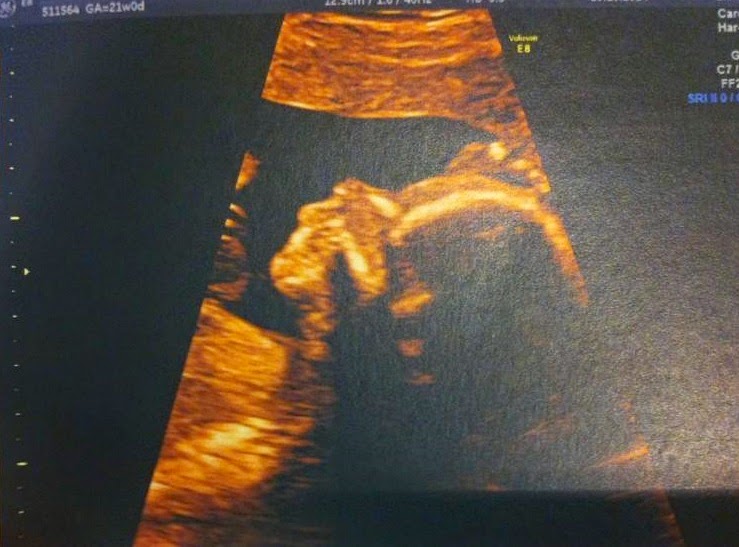

Agora que a

vida nos vai trazer um novo ser para criarmos e cuidarmos, dou por mim a pensar

o quanto quero que esta criança seja feliz. O quanto eu acho que é importante

passar-lhe os valores mais simples mas às vezes os mais difíceis. O quanto eu

quero que ela brinque, brinque e volte a brincar, porque foi assim que eu tive

a infância mais feliz de todas.